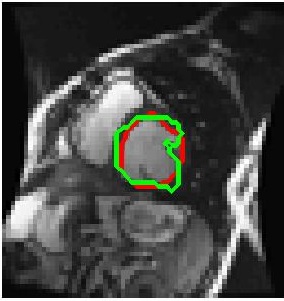

We train our ISR network from scratch. Each volume slice is treated as a separate image and transformed by random rotation and translation. We rotate the images between in steps of . For each rotation we translate the image by pixels in steps of . Thus on an average we get transformation for each image. Thus an average of slices per image gives a total of cardiac MR images. We show results on ISR for scale factor . Results for ISR are summarized in Tables 5. Following the approach for retinal landmark and pathology segmentation, we also show results for cardiac left ventricle segmentation (Table 6). For each segmentation approach we employ UNets as the segmentation framework and show results for different super-resolution methods as well as the low-resolution images (). Dice metric values for segmentation accuracy are shown in each case. Similar to retinal pathology segmentation we extract a patch covering the pathology and apply super-resolution for scale factors .

Figure 6 shows results for segmenting the cardiac LV from MRI. For each case we present results on the original HR images, SR images obtained by each of the methods being compared and also when using the LR images (scale factor ). It is quite obvious that the LR images are very fuzzy and don’t give accurate information on the anatomical boundaries. On the other hand the SR images from our method can predict a highly accurate reconstruction of the actual image. Other ISR methods show some degree of blur in the SR images. It is remarkable that deep neural network based methods are able to reconstruct original high quality images despite limited information in LR images. This is possible because of the ability of the generator networks to learn the relation between HR and LR images.